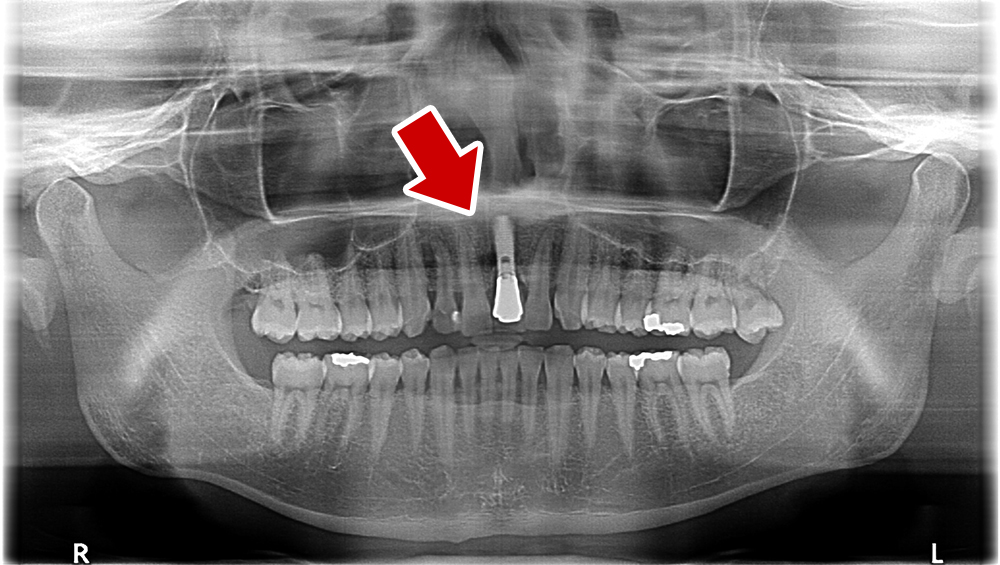

29歳 男性 歯科医療関係者紹介。また、お姉さんが歯科医療関係者。

- 主訴

- 左上1番目の歯が長期にわたり痛く、噛めない。

- 処置内容

1本インプラント埋入+再生療法。抜歯即時埋入、即時荷重法⇒抜歯を行い、

同時にインプラント埋入(即時埋入)、そして同時にインプラントへ仮歯を装着(即時荷重)

歯が無い期間なく、社会生活に支障が出ない

- 治療費用

- 約39万円(税込)

- 治療期間

9か月

手術当日に人工歯(仮歯)まで装着。 (通常待機期間は1年必要です。 (抜歯後6か月+インプラント(根)待機期間6か月+仮歯2か月))

- リスク

- 上部構造物、仮歯の破折、術後の腫れ(3日)、人工歯根脱落リスクがあります

- その他

- 学術雑誌、海外公演(アメリカ、ヨーロッパ)に多く紹介されたケース